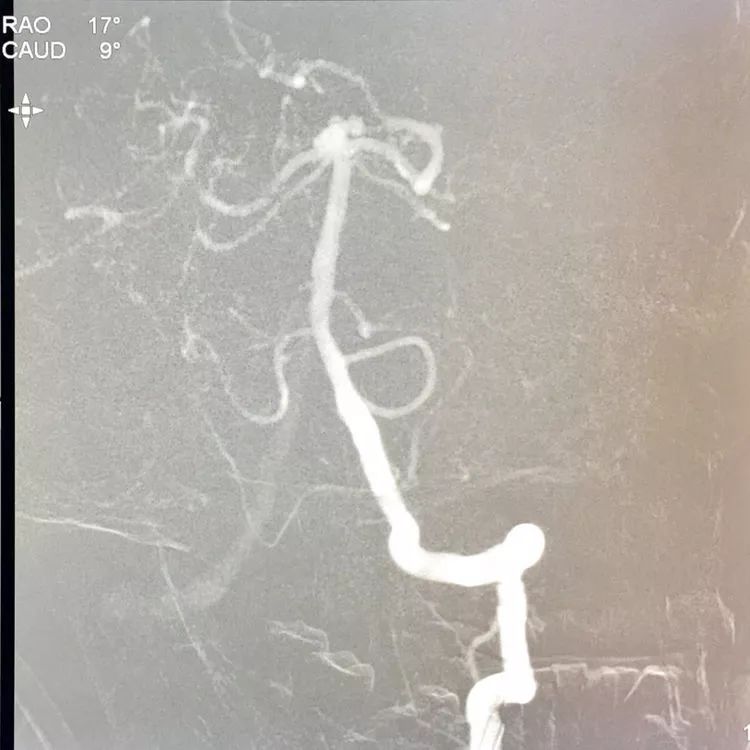

左椎动脉造影三维重建和测量